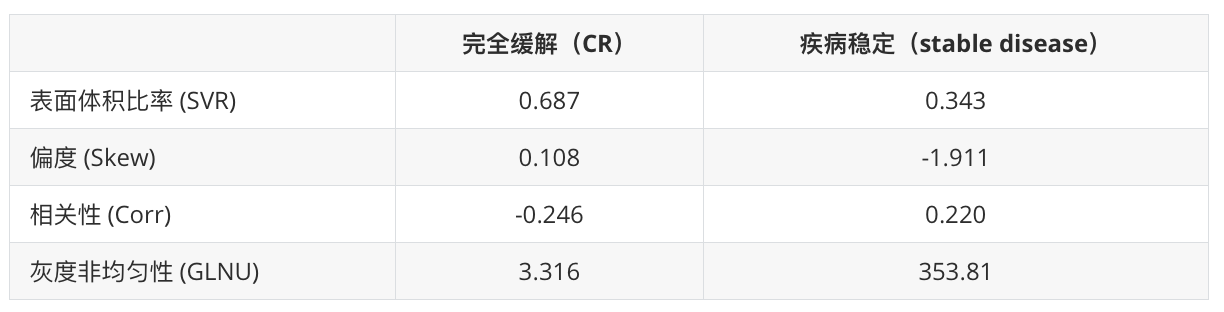

这四个放射组学特征与两组病变的关联在单变量分析(Mann–Whitney U检验)中报告了统计学意义(p< 0.05)。这些四个特征的详细诊断准确性统计数据在表2中报告,包括:

Fig. 2 展示了两个不同患者的肺部病变的轴向CT图像和3D图,以及它们的放射组学特征值。这些特征值用于区分完全缓解(CR)和疾病稳定(stable disease)的治疗结果。

放射组学特征值对比

通过比较两组病变的放射组学特征,研究人员可以寻找与治疗反应相关的模式。例如,CR组的病变可能具有较高的SVR值和较低的灰度非均匀性,而疾病稳定的病变可能具有较低的SVR值和较高的灰度非均匀性。